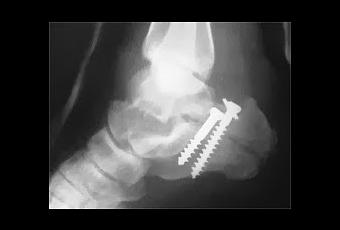

Le jeune radiologiste est très gentil, mais les positions qu'il exige que je prenne avec ma jambe pour prendre les radios sont vraiment très douloureuses! Ça ne prend toutefois que quelques minutes et je retourne dans la salle numéro huit pour attendre le médecin... Quarante-cinq minutes plus tard, il arrive finalement avec la nouvelle. C'est bel et bien une fracture et j'ai probablement quelques ligaments étirés. De plus, l'os est mal cassé et les deux morceaux ne sont pas alignés. L'opération e tla pose d'une place de métal est probablement requise! Quoi??? Moi qui était certain de ressortir en quelques minutes avec un plâtre! Le spécialiste passera me voir demain matin et ils doivent donc me garder pour la nuit. Double Quoi??? Je dois dormir ici? J'appelle Marie-Josée dans le camion pour lui annoncer et qu'elle vienne chercher quelques trucs avant de retourner à la maison se reposer. Le médecin lui dit qu'elle pourra venir me voir demain matin au lit 'K'. C'est quoi ça le lit 'K'??? Il me fait un plâtre temporaire et me dit d'attendre qu'un préposé vienne me chercher pour me reconduire au fameux lit. Il me donne aussi deux couvertures en me rappelant de ne pas les oublier lors du transfert. Je pourrais en avoir besoin!Plusieurs minutes plus tard, le préposé arrive et me transporte dans ma chaise roulante jusqu'aux urgences. L'endroit ou on voit les gens entassés dans les corridors, ça vous dit quelque chose? Et en effet, me voilà en face du lit 'K'... en plein milieu du corridor, sous des néons étincelants et tout proche du poste des infirmières! C'est vraiment spécial. Je reste plutôt zen, me disant que c'est une expérience de vie. Mais c'est plutôt difficile de dormir. Mais bon, l'épuisement aidant, car il est 5h00 du matin, je finis par m'endormir au son des moniteurs cardiaques.

Malheureusement, les photos de la radiographie et de la salle d'urgence ne sont pas de moi.